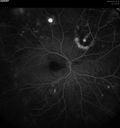

Macroaneurysm FA620 viewsMacroaneurysm with Subretinal Hemorrhage and ME in OS of an Elderly Female

|